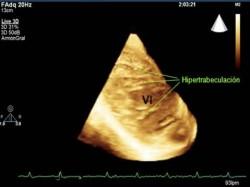

La hiper-trabeculación de ventrículo izquierdo (HACVI) es una característica típica de ciertos tipos de miocardiopatía (enfermedad crónica del músculo del corazón). La anormalidad es la causa principal de muerte súbita cardíaca relacionada con el ejercicio en atletas.

Los investigadores observaron a 692 atletas en el Reino Unido y encontraron que casi el 7 por ciento de ellos tenía la anomalía, en comparación con el 0,4 por ciento de los no atletas. Y la condición se halló mucho más común en los atletas masculinos negros (13 por ciento) que en los otros atletas (4 por ciento).

La alta prevalencia de HACVI entre los atletas sugiere que esto puede representar una parte del espectro de las adaptaciones cardíacas que se sabe que constituyen “corazón de atleta”. El entrenamiento deportivo regular conduce a cambios en el funcionamiento y la estructura del corazón.

Teniendo en cuenta que HACVI es una característica de la muerte súbita cardíaca, su prevalencia entre los atletas crea mayores retos para los médicos que tratan de diferenciar entre el corazón de atleta y una condición médica seria, sobre todo en los atletas masculinos negros, donde la prevalencia es mucho mayor.